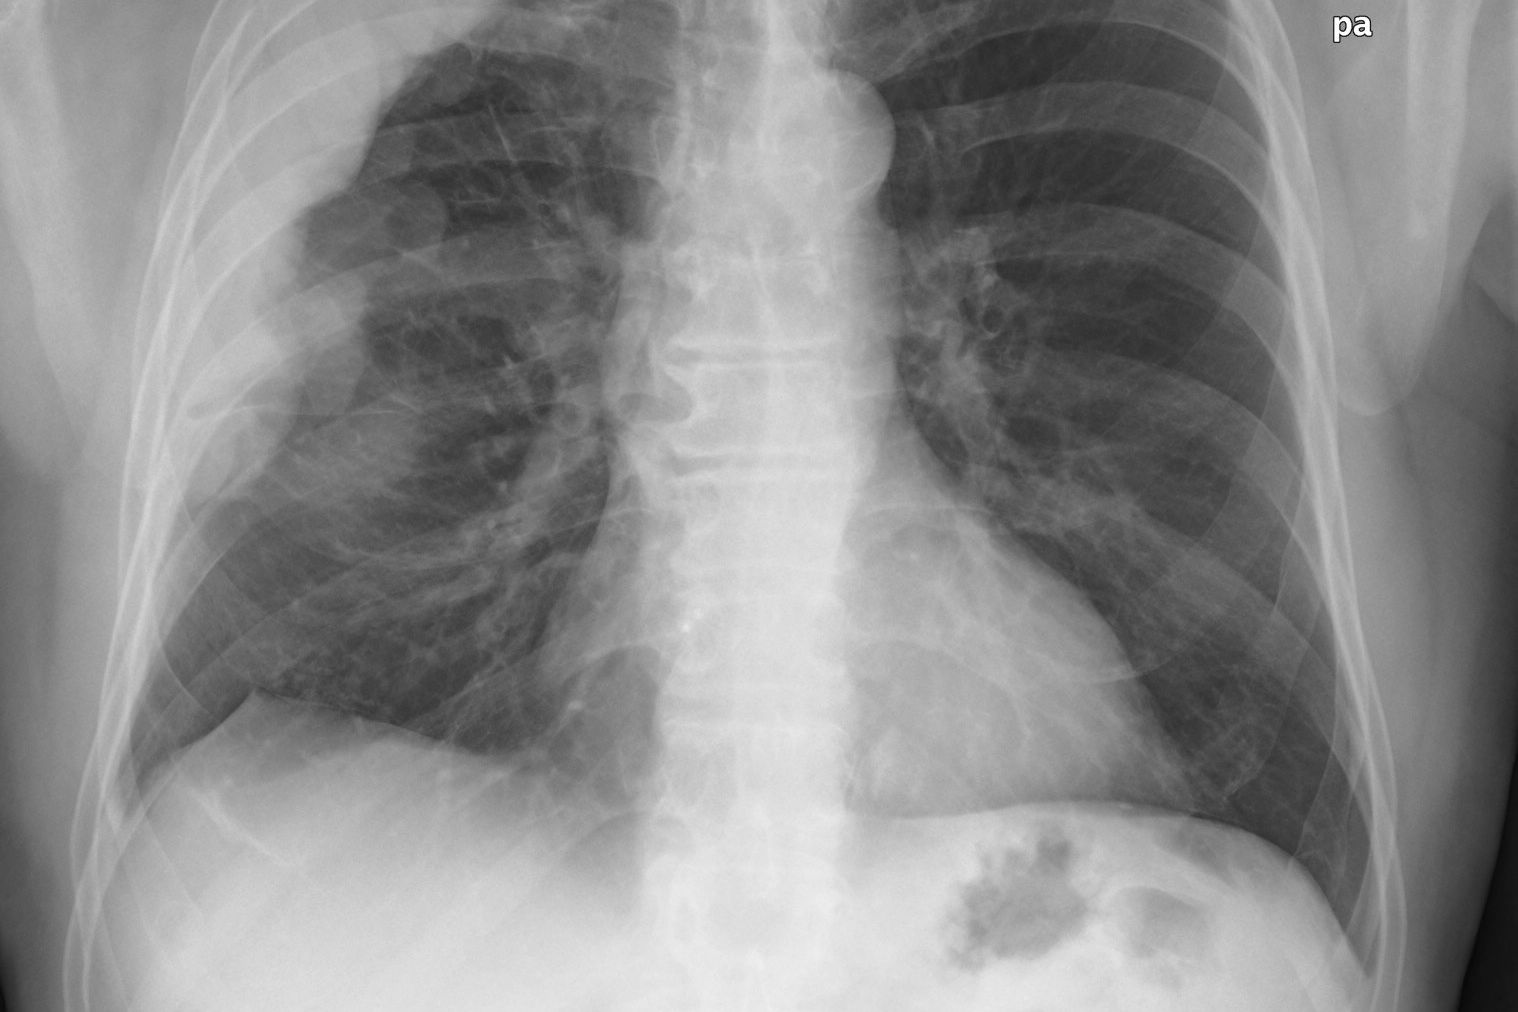

Malignant pleural mesothelioma is a particularly aggressive tumor that occurs in the lining that covers the lungs. It typically results from exposure to asbestos. Standard anti-mesothelioma treatment includes surgery, chemotherapy, irradiation or multimodal therapy, which is the combination of these approaches. Because these conventional therapies have reached their efficacy plateau, new targeted approaches are needed to improve survival. However, despite proven efficacy of molecularly targeted drugs across a wide spectrum of other cancer types, most mesothelioma patients could not yet benefit from this novel treatment paradigm. The new research suggests that by preventing the growth of new mesothelioma blood vessels and thus starving tumors of nutrients and oxygen, the novel targeted medication called nintedanib is a promising candidate for helping patients with mesothelioma.